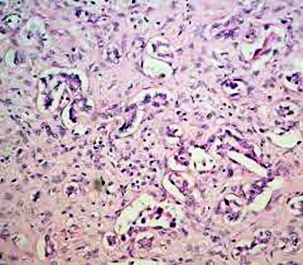

황달이란? (jaundice)

몸에 필요한 황색의 담즙색소 (빌리루빈)이 과도하게 쌓여 눈동자나 피부 등에 착색되는 현상을 말한다고 합니다. 이 담즙색소는 체내에 들어온 물질들이 분해되는 과정에서 생성되는 필요 없는 물질인데요. 일반적으로는 간에서 해독작용을 거친 후에 담즙으로 배설이 되는 것이 정상적이지만, 그렇지 못한 경우 황달이 발생하게 된다고 합니다.

황달이 생기는 이유는 담즙색소라고 알려진 빌리루빈이 과도하게 생기기 때문입니다. 빌리루빈은 우리 몸의 오래된 적혈구가 파괴되면서 생기는 물질인데요. 이 물질은 담즙에 녹아서 우리 몸의 배설물과 함께 배출이 되는 것이 정상적이지만 빌리루빈의 과잉생산이나, 간의 장애, 간세포나 담도의 손상에 의해 빌리루빈이 역류할 경우 발생된다고 합니다.